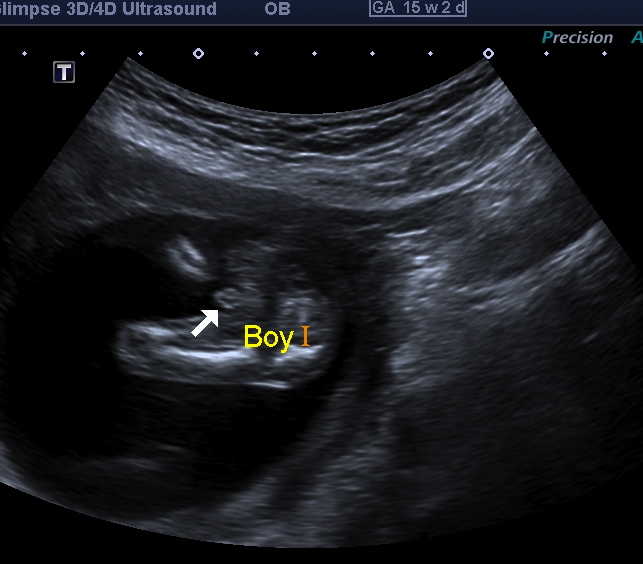

12w - nub

Attachment 7618